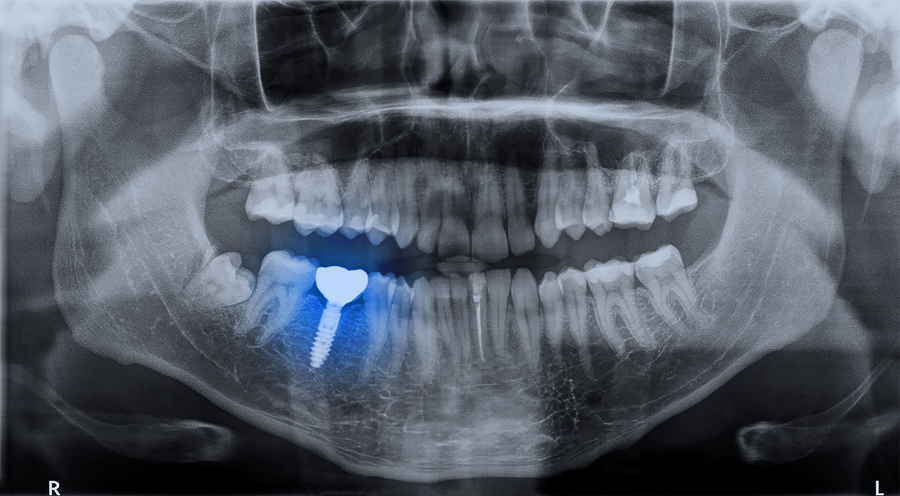

- How quickly the implant bonds to your jaw bone. Once your jaw is strong enough to accept a dental implant, the implant post will be placed. The process of osseointegration (the bone integrating with the implant) is what secures the implant and allows your new tooth to have a solid foundation.